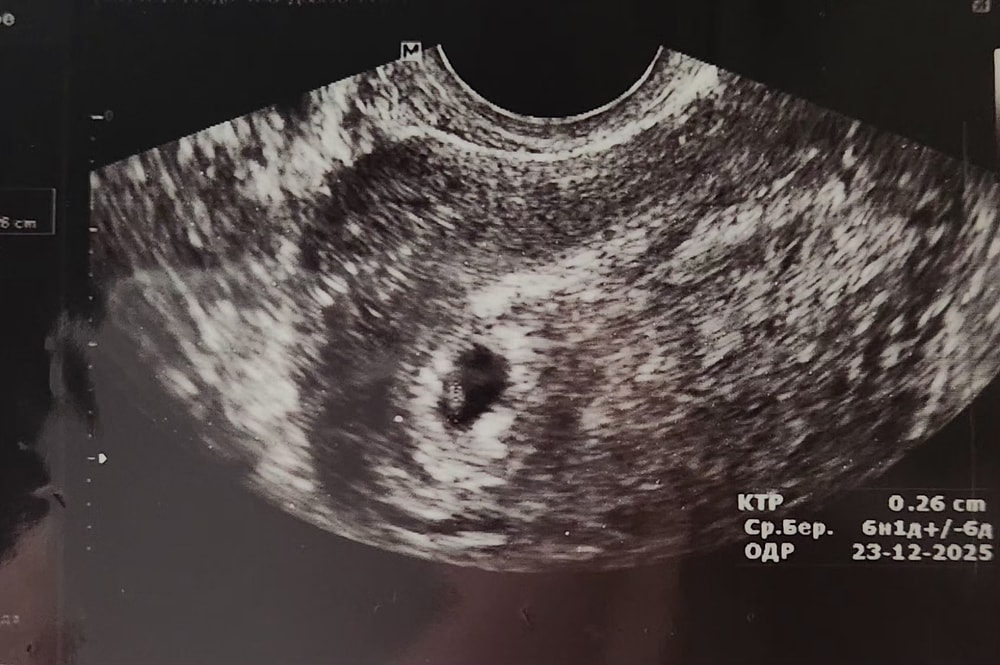

Сходила на УЗИ посмотреть бейбика, все ок, растет. Мазало потому что пя переместилось из верхней части матки куда-то ниже и правее.

12.05 на следующее УЗИ, слушать сб, а то сейчас только пульсацию поймали на таком маленьком сроке